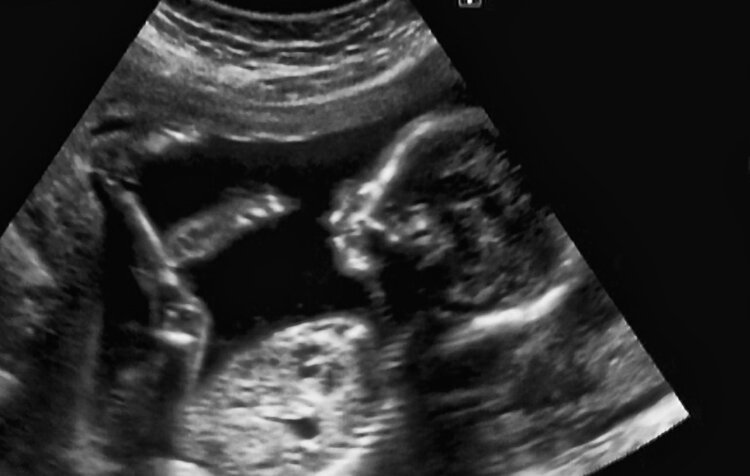

3、产科、妇科

除此之外,超声还是孕期“神器”,通过检查可在产前发现胎儿是否有畸形倾向,观察胎儿各阶段的生长发育情况等。